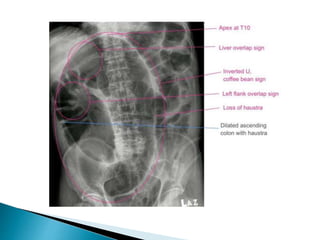

Inverted U-shaped appearance of distended

sigmoid loop

 Largest and most dilated loops of bowel are

seen with volvulus

 Loss of haustra

 Coffee-bean sign à midline crease

corresponding to mesenteric root in a greatly

distended sigmoid

 Sigmoid volvulus – bowel loop points to RUQ

large, dilated loop of large bowel with an inverted U-shape

with walls between two volvulated loops pointing from LLQ toward RUQ;

same patient with decompressed sigmoid volvulus following insertion of rectal tube